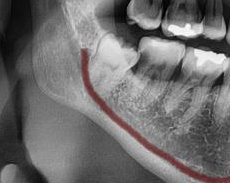

次にパノラマ写真を撮影してみると、手前の歯より低い位置でまっすぐに生えているのが確認できました。